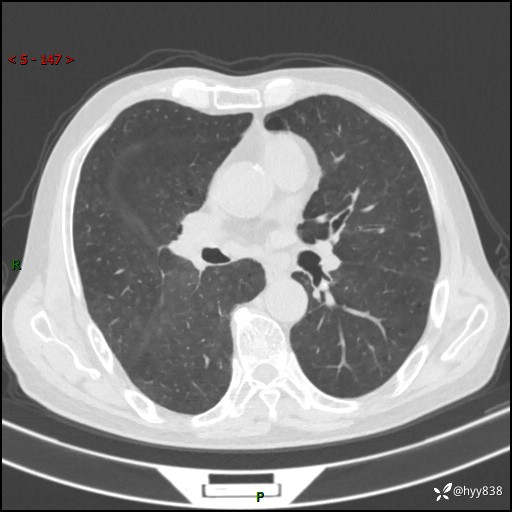

儿女怕老人寂寞,养了两只鹦鹉,呼吸科主任问我典不典型---结果公布~

武医生 等 4 位达人已点赞患者性别:男

患者年龄:71岁

主诉:喘气半年余,咳嗽乏力伴味觉减退2月余

简要病史:者半年前左右无明显诱因出现呼吸困难,轻微运动后出现喘气,未予以重视。2月余前受凉感冒后出现咳嗽,咳白色泡沫痰,不易咳出,于当地医院行输液治疗,未见明显好转,并感觉全身乏力,体力下降,并感口苦,味觉减退。近10余天前感咳嗽喘气加重,咳白色泡沫痰,不易咳出,口苦,味觉减退加重。为进一步检查及治疗,入我院就诊,门诊以“呼吸困难”收入院治疗。 起病以来,患者精神,睡眠,饮食欠佳,大小便可,体力下降明显,体重稍下降。

辅助检查:CT

临床诊断:呼吸困难

讨论:诊断?

胸部CT平扫